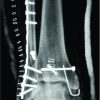

In comparison with open reduction and internal fixation, there would be anatomic reduction and absolute stability of the fracture with preserved ankle range of motion, but higher risk of hardware failure and loss of reduction requiring subsequent revision surgery if the patient were to weight bear post-operatively [3]. Ultimately, the family elected to proceed with the TTC nail due to its stability and durability and so that the patient could bear weight through the right lower extremity post-operatively. Intraoperative fluoroscopy images demonstrating near anatomic alignment of the tibiotalar joint are demonstrated in Figure 3. Post-operatively, the patient was placed into a bulky soft dressing and was given a walking boot without any weight-bearing restrictions. The remaining hospital course was uneventful, and she was discharged to home.

Two-week follow-up revealed the skin incisions to have nicely healed and the fracture blisters to have subsided. Radiographs shown in Figure 4 demonstrated maintained alignment and position of the implant without any complications. Eight-week follow-up revealed no skin complications and the patient was ambulatory without difficulty. Radiographs at this time demonstrate healed fractures in anatomic alignment as shown in Figure 5.